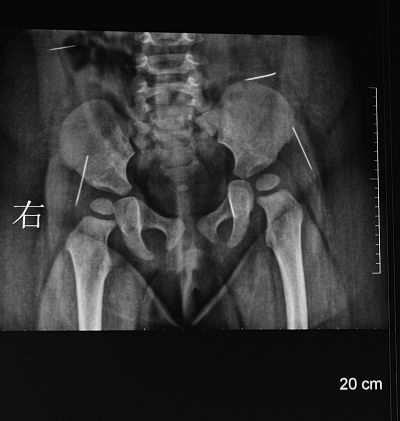

“一根、兩根、三根、四根,這是右側腰部一根,這是左側腰部,這是臀部的,像縫衣針,還有像大頭針,三厘米,臀部這兩根很長,腰上兩根1.5厘米差不多……”淮安市婦幼保健院手術醫生夏順林拿著女嬰的X片向記者介紹。